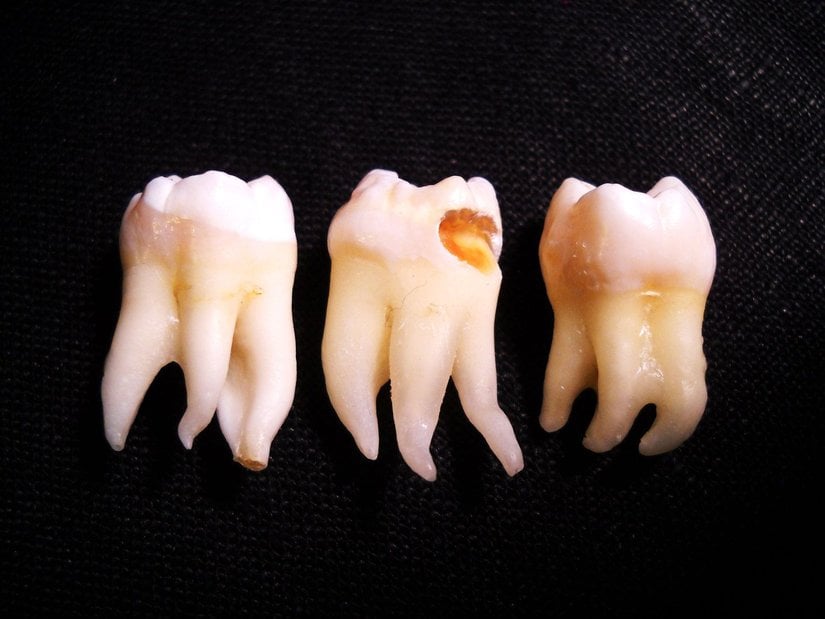

Uzun yıllar insanlar bu dişlerin en başından neden var olduğunu anlayamamış ve bir çeşit "lanet" olarak görmüşlerdir; zira 20 yaş dişlerinin çıkmaya başlamasından çekilene kadar verdiği acıyı, bu dişleri sorunlu olarak çıkan kişiler gayet iyi bilirler. Ancak evrimsel biyolojinin gelişimiyle birlikte öncelikle insan evrimine ışık tutulmuş, daha sonra da bu tip körelmiş organların varlığı açıklanmıştır. 20 yaş dişleri de, insanda görülen 40'tan fazla körelmiş organ ve yapıdan sadece birisidir. Aşağıda, bu körelmiş yapıların ne şekilde hatalı oluşabileceklerine örnekler görülmektedir: